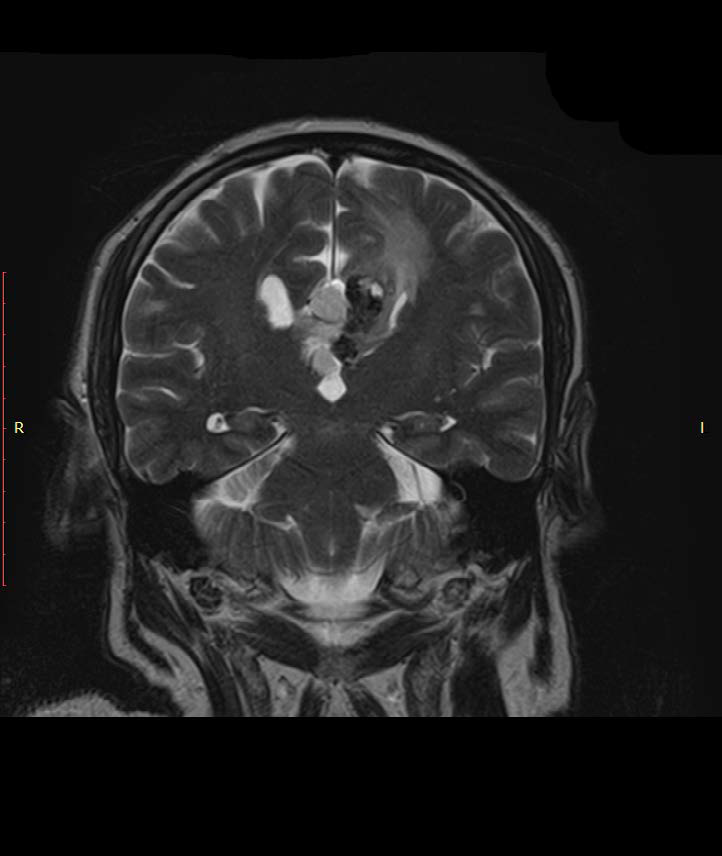

The Role of MRI in Diagnosing Calcifying Pseudoneoplasms of the Neuraxis (CAPNON): A Rare Case Report of CAPNON with Corpus Callosum Agenesis and a Lipoma

Jeton Shatri, Kreshnike Dedushi Hoti, Ardita Kafexholli, Jeton Kafexholli, Veton Kurti, Diar Kabashi, Dijon Musliu